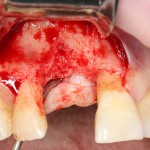

Например, в следующей ситуации:

Оставить так, как есть — это значит, сильно рисковать имплантом и объемом альвеолярного гребня — фактически, большая часть импланта пятого зуба «висит в воздухе». Поэтому получившуюся костную полость мы заполняем аутокостной стружкой в смеси с Bioss и закрываем коллагеновой мембраной BioGide:

При необходимости, мембрану можно фиксировать пинами.